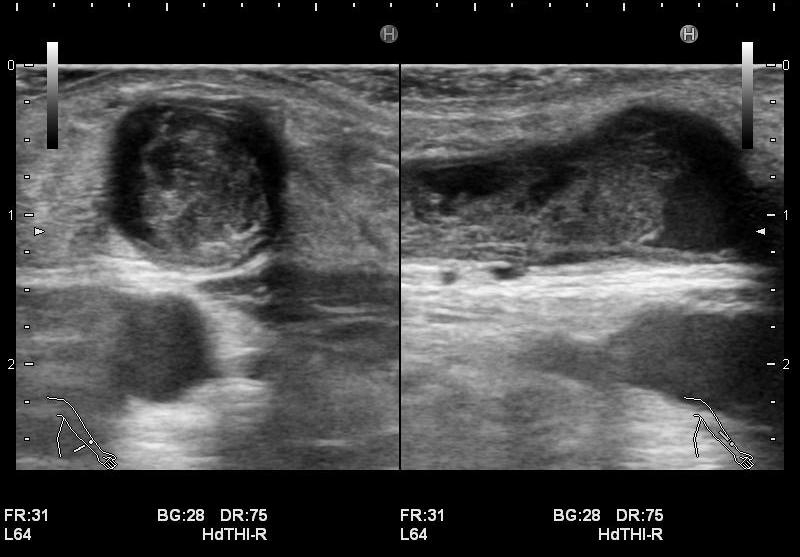

石灰化画像

・静脈系の観察

吻合部から中枢へ向かって走査し、血管の走行や太さ、血管までの深さ、狭窄や石灰化、血栓等の有無を観察しています。長軸断面、短軸断面それぞれで観察し、また、カラードプラも使用しできるだけ正確に、血管内の状況を把握するようにしています。